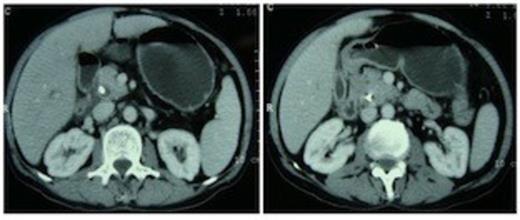

A 55 year non-diabetic male with painless progressive jaundice, pruritus and weight loss of 3 month duration was admitted in emergency with cholangitis. Investigations revealed a total leukocyte count of 17 000/cu.mm, total bilirubin: 222.3 μmol/L, direct: 136.8 μmol/L and alkaline phosphatase level: 1153 U/L. Side viewing endoscopy showed an ulceronodular growth at papilla, a papillotomy and endoscopic biliary plastic stenting was done. Neither cholangiogram nor pancreaticogram was obtained in view of cholangitis. Once his cholangitis resolved, he was referred for surgery. Pre-operative triple phase CT (computed tomography) scan of the abdomen showed a resectable ill-defined hypodense mass in the region of ampulla, the pancreatic head and uncinate were normal however the neck, body and tail of pancreas were absent (figure 1,2).

Computed tomography scan showing pancreatic head and uncinate process with absence of neck anterior to the portal vein. An ill-defined hypodense mass is seen in the ampullary region. Biliary stent is in situ.